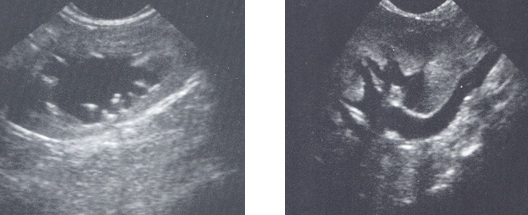

What is being shown here?

R = Dilated renal pelvis

Bottom = dilalted proximal ureter

L = ureters dilated by couple mms —> obstruction of urinary outflow